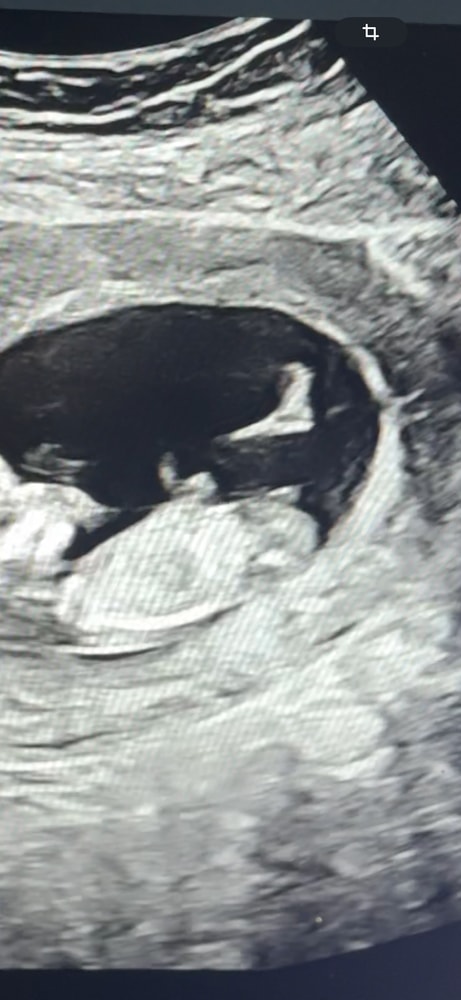

Прикрепляю свои узи, на разных узи разное положение полового бугорка, говорят мальчик, но допустим на второй фотке мне кажется половой бугорок на девочку) что думаете? Читаю разное мнение, что у кого то был прям вверх половой бугорок, а итог девочка и наоборот

В 15,3 у нас была уже четко девочка, то есть не половой бугорок, а вполне себе четкие половые признаки, не перепутать. У вас на втором фото ракурс не четко профиль, мне кажется, а чуть повернут, соответственно выводы делать нельзя. По другим фото похож на мальчика, но опять же на таком сроке 1: ошибки явление частое 2: мы ж не врачи) повторите УЗИ недель в 15-16, там уже четко всё видно, половые органы сформированы.

У вас на первом фото половой бугорок, а на втором - часть ножки, полового бугорка там не видно. Мальчик у вас. Мне в 12+6 правильно пол сказали.